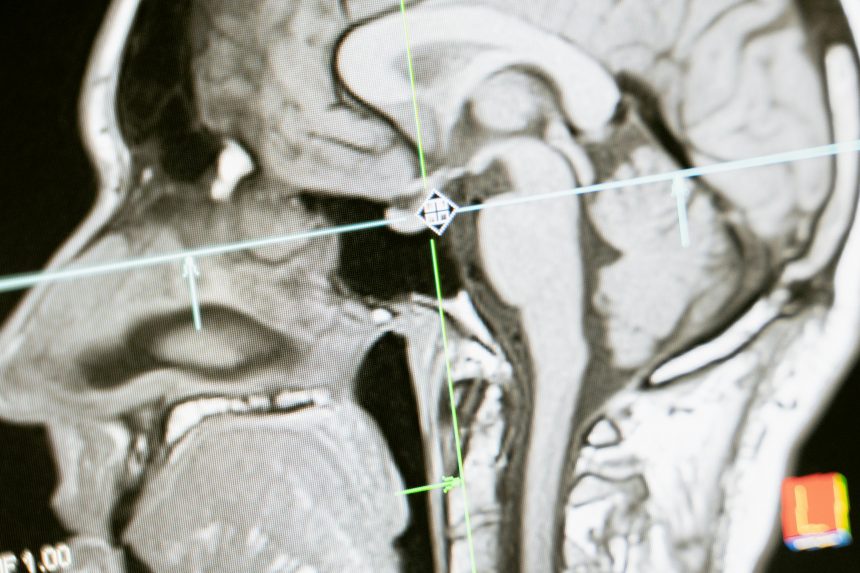

Метод фокусированного ультразвука позволяет временно открыть доступ сквозь гематоэнцефалический барьер, не повреждая окружающие ткани. Это создаёт окно для целевой доставки препаратов, включая креатин, непосредственно в мозговую ткань.

Эта технология уже рассматривается как потенциальное средство лечения опухолей мозга у детей, а также нейродегенеративных заболеваний. Исследователи уверены, что с её помощью можно будет улучшить прогноз у пациентов с дефицитом транспортера креатина — редким, но тяжёлым генетическим расстройством.